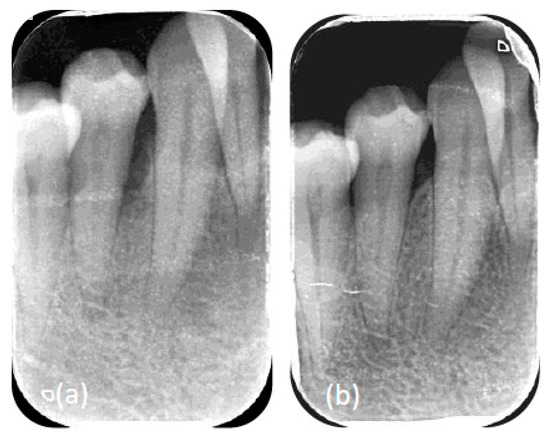

- PSI: Modified papilla preservation, including an attempt to regenerate with amelogenin (Enamel Matrix Derivative) at the residual deep intrabony defect (≥3 mm), mesial to 15; procedure according to Cortellini and Tonetti [30].

- PSI: Modified papilla preservation, including an attempt to regenerate with amelogenin (Enamel Matrix Derivative) at the residual deep intrabony defect (≥3 mm), mesial to 44; procedure according to Cortellini and Tonetti [30].